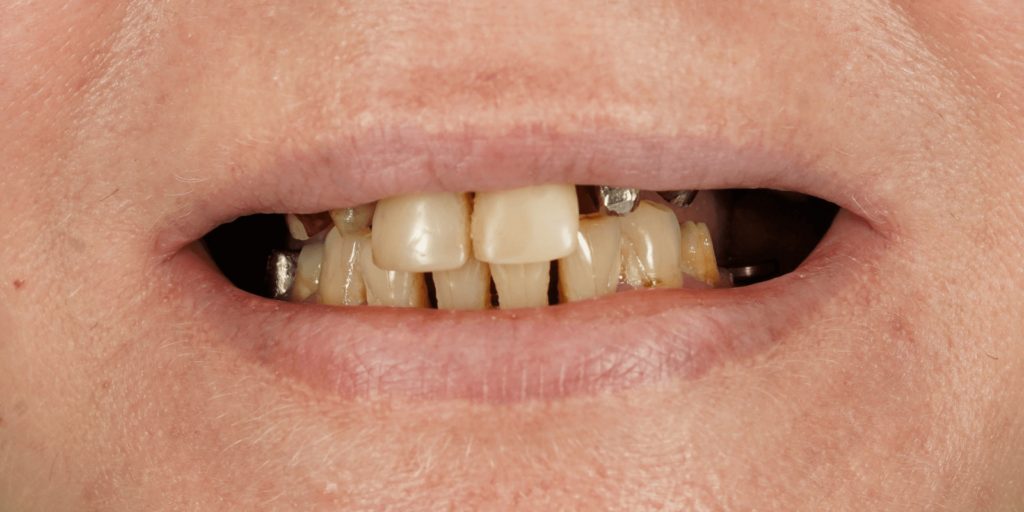

Пациентка обратилась в нашу клинику с жалобами на эстетический дефект зубного ряда, подвижность зубов и на боль в челюсти. Во время осмотра врач выявил:

- На верхней челюсти: 2 мостовидных протеза, 4 отсутствующих зуба, зубную коронку на зубе 2.6, также были обнаружены кариозные полости в двух передних зубах.

- На нижней челюсти: 2 мостовидных протеза и 4 отсутствующих зуба. Зуб 3.8 подвижен, контактирует с антагонистом на верхней челюсти.

Все ортопедические конструкции были из металлокерамики и подлежали замене по нескольким причинам:

- Неудовлетворительное состояние зубов под конструкциями, неудовлетворительный эстетический эффект, изношенность конструкций, необходимость удаления некоторых опорных зубов.